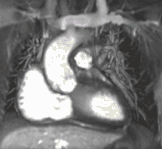

Atrial septal defect with dilation of the right ventricle by CMR

Partial Anomalous Pulmonary Venous Drainage by CMR